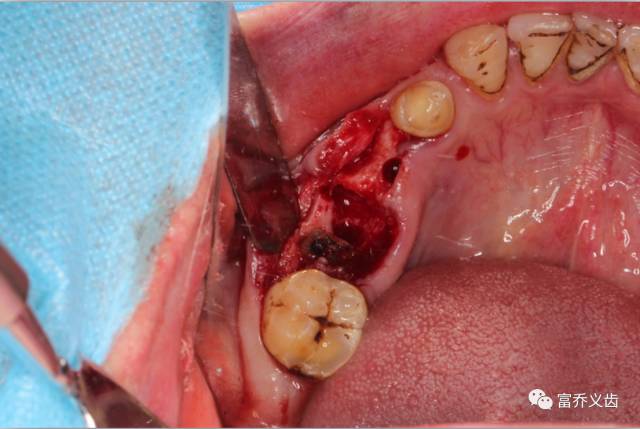

种植术前口内照片,切开后拍的照片

种植术中46远中牙根未拔除先备洞